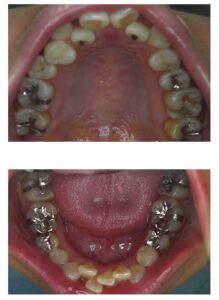

• 金属アレルギー 全快

金属アレルギー 全快

金属アレルギーの患者様は、当医院では年間で数名程度と比較的少ないのですが、金属アレルギーと判るまで結構悩まれて、色々な病院を回られることもあるようです。 症状は、手のひらや足の裏とか、皮膚の薄い弱い部分とか、全身にでるものなど様々です。 最 […] 本文を読む